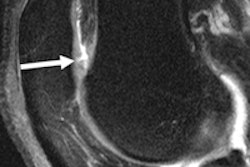

During his RSNA presentation, Subhas cited previous research that found that preoperative knee MRI can reduce the number of surgeries and uncover a significant number of unsuspected diagnoses, improving the diagnostic confidence for meniscal and anterior cruciate ligaments.

"For example, if the clinician was worried about a lateral meniscal tear or [patients] were having lateral side knee pain, most of the time when they thought there was a lateral meniscal tear, there was no sign [of a tear] on the MRI," Subhas told AuntMinnie.com.